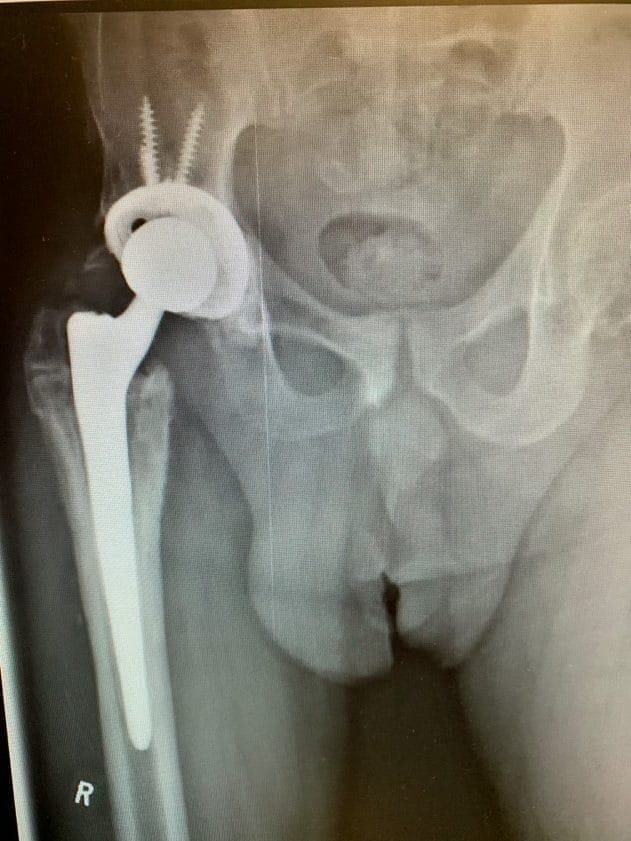

During her surgery, we first identified the insertion sites of the various components of her femur fracture hardware, and removed these carefully in the appropriate sequence. Once they were fully removed, we then began the hip replacement part of the procedure. Her acetabular component was placed without event, her femoral component proved more challenging to prepare for, given the new bone her body had formed in the area of the fracture. With careful removal of the bone blocking the femoral canal, we managed to implant a special femoral component that bypassed the site of the fracture, significantly reducing the risk of her femur fracturing again in the same area.

Post-op